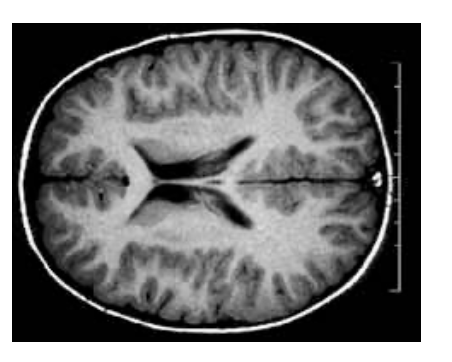

axial (horizontal)